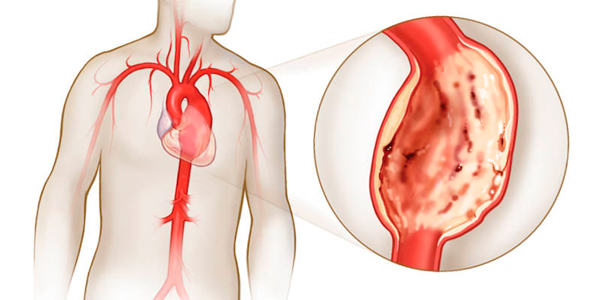

Атеросклероз сосудистой стенки является основной причиной (до 80% случаев аневризмы аорты вызваны именно атеросклерозом). Под воздействием холестериновой бляшки, образующейся на аорте, начинаются дегенеративные процессы, которые ослабляют стенку сосуда, лишая ее эластичности и приводя к выпячиванию. В результате формируется аневризма.

- атеросклероз. Избыточные отложения холестерина на стенках сосудов приводят к их истончению и последующему расширению просвета;